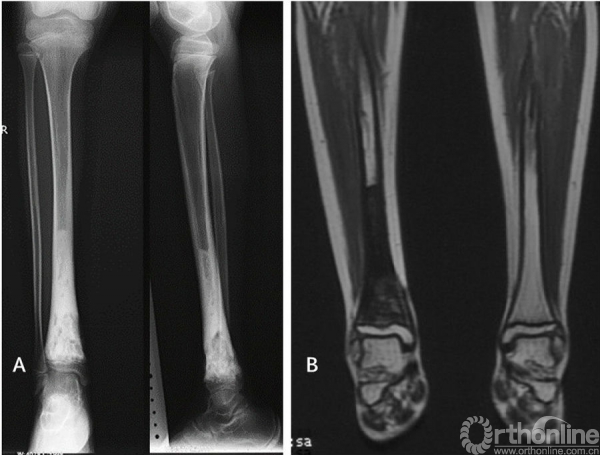

图1女性/9岁,右胫骨下端骨肉瘤。A术前X光片,右胫骨下端骨肉瘤。B化疗后MRI显示软组织包块消失,病变局限于骨内。C术中完整切除胫骨远端肿瘤后刮除髓腔内肿瘤、65℃ 20%高渗盐水灭活30分钟后原位回植、对侧自体腓骨置于髓腔中心、钢板内固定、LARS韧带重建内踝软组织、下胫腓关节融合。D术后即刻X光片。E术后4个月X光片显示截骨面已愈合。F术后踝关节功能良好,4个月后无需支具辅助可正常行走。